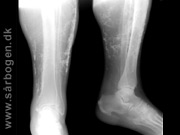

Charcot i mellemfod

Charcot i mellemfod ...

Charcot i ankel

Charcot i ankel (rtg...